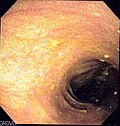

| Endoscopy | brown discolouration of the mucosa, esp. proximal colon and cecum |

- Endoscopist may see brown pigmentation of mucosa and suspect the diagnosis.

- Brown pigmentation of the mucosa, especially cecum and proximal colon.[2]

- Less pigmentation distal.

Endoscopic image